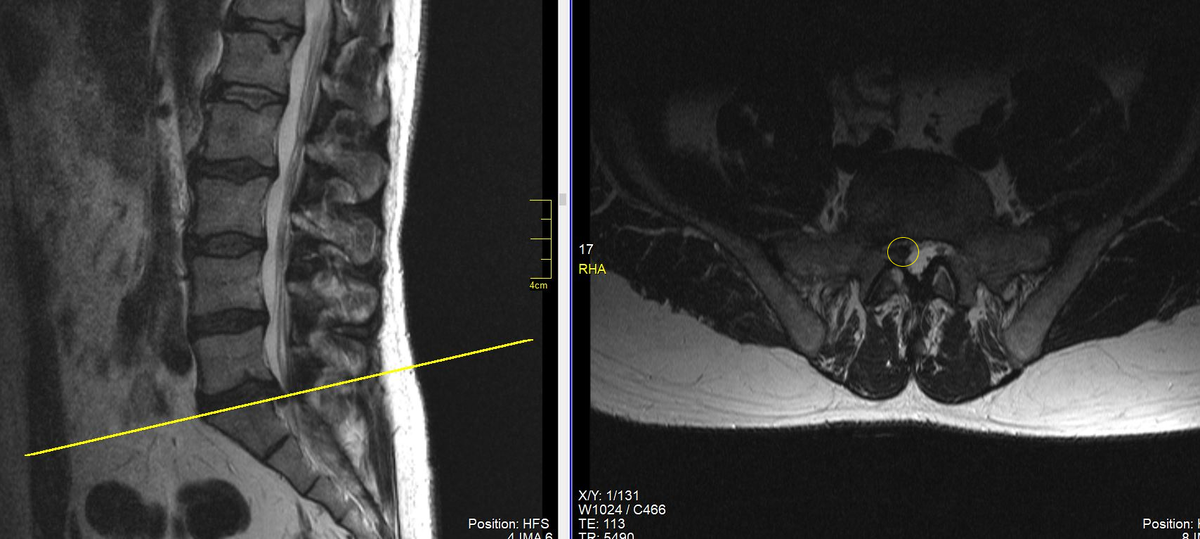

МРТ пояснично-крестцового отдела позвоночника: секвестрированная грыжа межпозвонкового диска между 5 поясничным и 1 крестцовым позвонками без сдавления нервных корешков, положение грыжи срединное.  В такой ситуации операции можно избежать. (данные собственного архива).